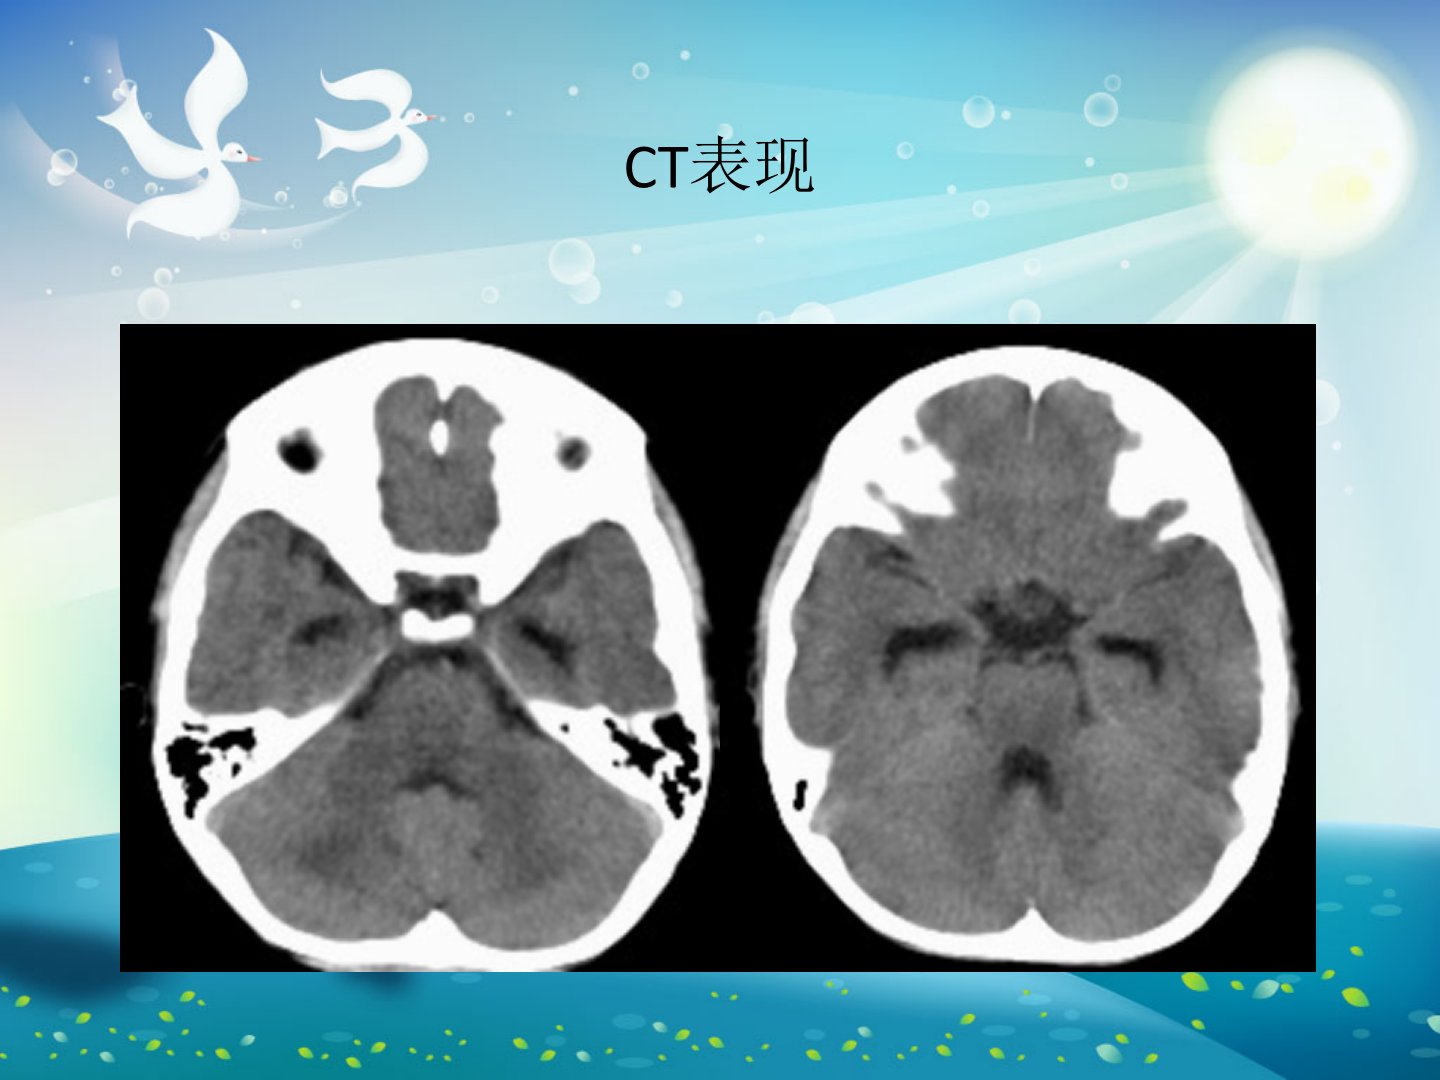

本文报告两例小儿急性坏死性脑病(ANE)病例。病例1为6岁男童发热2天后出现抽搐、昏迷入院诊断为急性坏死性脑病综合治疗3天后死亡。病例2为2岁男童发热3天后呕吐咖啡样物、抽搐、昏迷2小时入院确诊为急性坏死性脑病经20天综合治疗无好转呈植物人状态康复治疗无改善。ANE病死率高目前报道病例约400例国内仅10余例病因尚不清楚可能与病毒、支原体感染有关发病机制可能与感染触发自身免疫有关。ANE诊断尚无统一标准但具有急性起病、进展迅猛、发热、抽搐、迅速进入昏迷等特点影像学以丘脑对称性损害为主。文章还讨论了ANE与Reye综合征、ADEM、Leigh病、流行性乙型脑炎及肿瘤的鉴别诊断。